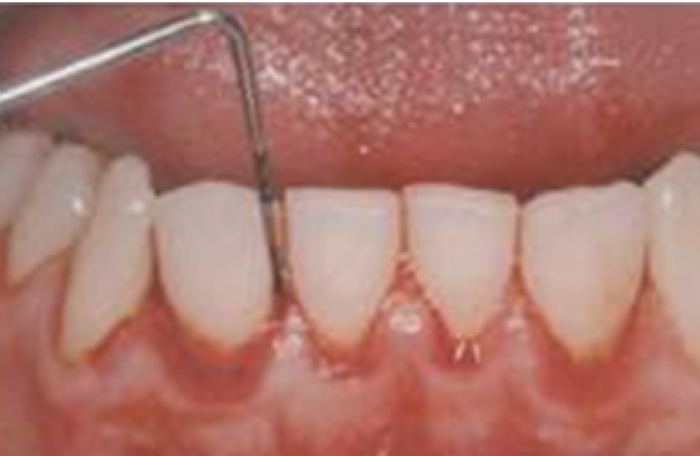

中等度歯肉炎の症状

プロービングによる、大量の出血、発赤、腫脹が特徴です。